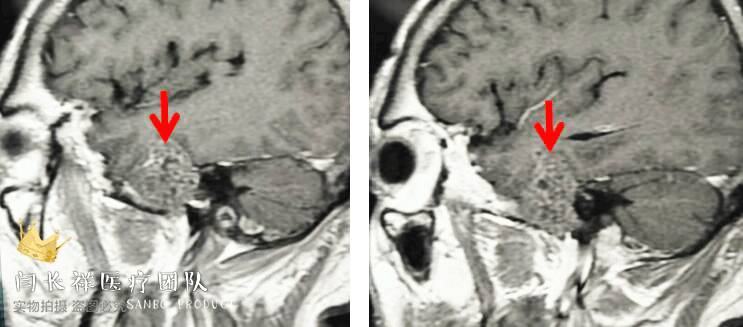

术前MRI轴位T1扫描示病灶呈等信号。

术前MRI轴位T2扫描示病灶侵及面神经膝段及中耳骨质。

术前MRI轴位T1增强示病灶显著不均匀强化。

术前MRI矢状位T1增强。

术前MRI冠位T1增强示病灶主体位于硬膜外,侵蚀中颅窝底骨质并朝颞下窝、翼腭窝生长。